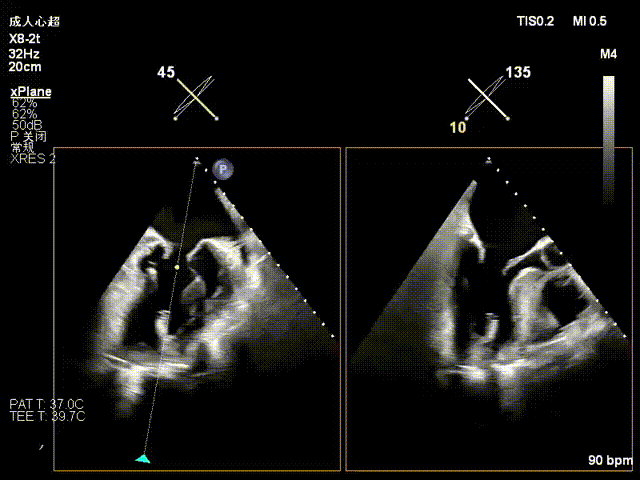

收紧夹子并确认夹合效果

评估后解离释放夹子

术后即刻反流降为少量,剩余瓣口面积2.57cm²,平均跨瓣压差2mmHg。

术后复查超声心动图显示:二尖瓣轻度返流,三尖瓣中度返流,二尖瓣可见金属夹回声,启闭正常;各心室大小正常,升主动脉不宽,主瓣回声增强,启闭良好;二尖瓣舒张期峰值流速1.4 m/s,功能面积2.1 cm²,跨瓣平均压差约4 mmHg。

术后心功能改善明显:LVdD 46mm,FS 33%,LA 45mm,LVDs 31mm,LVEF 62%。